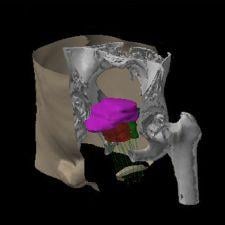

Varian Medical Systems will be exhibiting its complete line of hardware, software, and applicators for HDR and LDR brachytherapy, including the VariSource iX, GammaMedplus iX and the GammaMedplus 3/24 iX HDR afterloaders, the BrachyVision treatment planning system plus the Vitesse module for using transrectal ultrasound (TRUS) images as the basis for a prostate cancer treatment plan. For LDR treatments, the VariSeed treatment planning system is a leading system for this highly specialized form of brachytherapy.